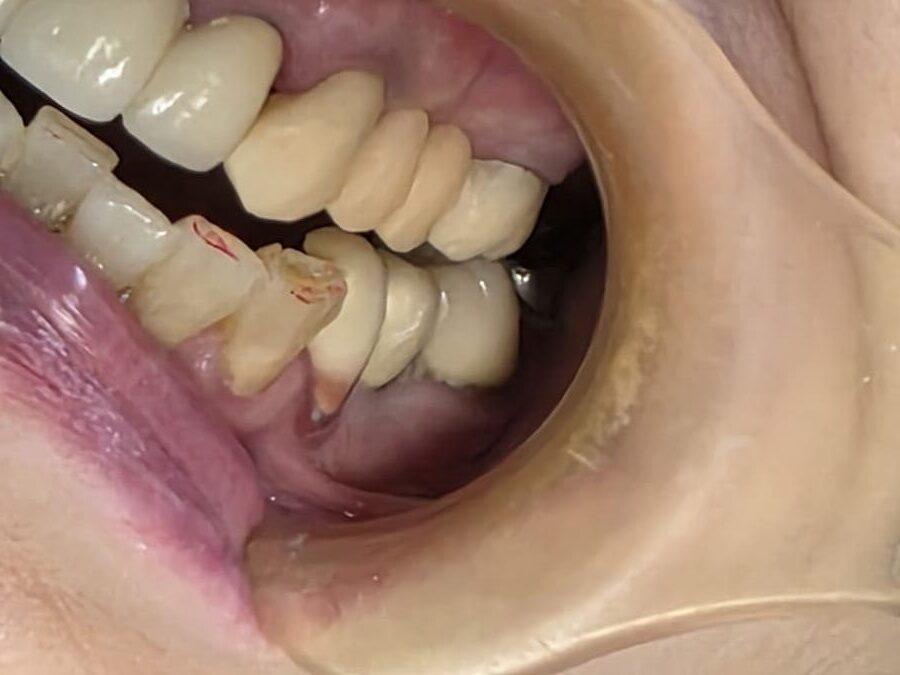

症例 左下奥歯3本のメタルインレー をセラミックインレーで 再修復した症例 左下6,7,8番を モノリシックジルコニア インレーで修復し審美的および 機能的改善を行ったケース

Before

After

| 治療期間・回数 | 治療期間14日で2回来院。 |

|---|---|

| 費用 (自由診療となります) |

総額 231000円(税込み) 診査・診断・術前術後の説明費用含む。 |

| リスク・副作用 | セラミックの破折、脱離。2次う蝕。 |

症例 メタルインレーの入っている左下一番奥の歯をセラミックインレーで修復した症例

総額 77000円(税込み) 診査・診断・術前術後の説明費用含む。 |